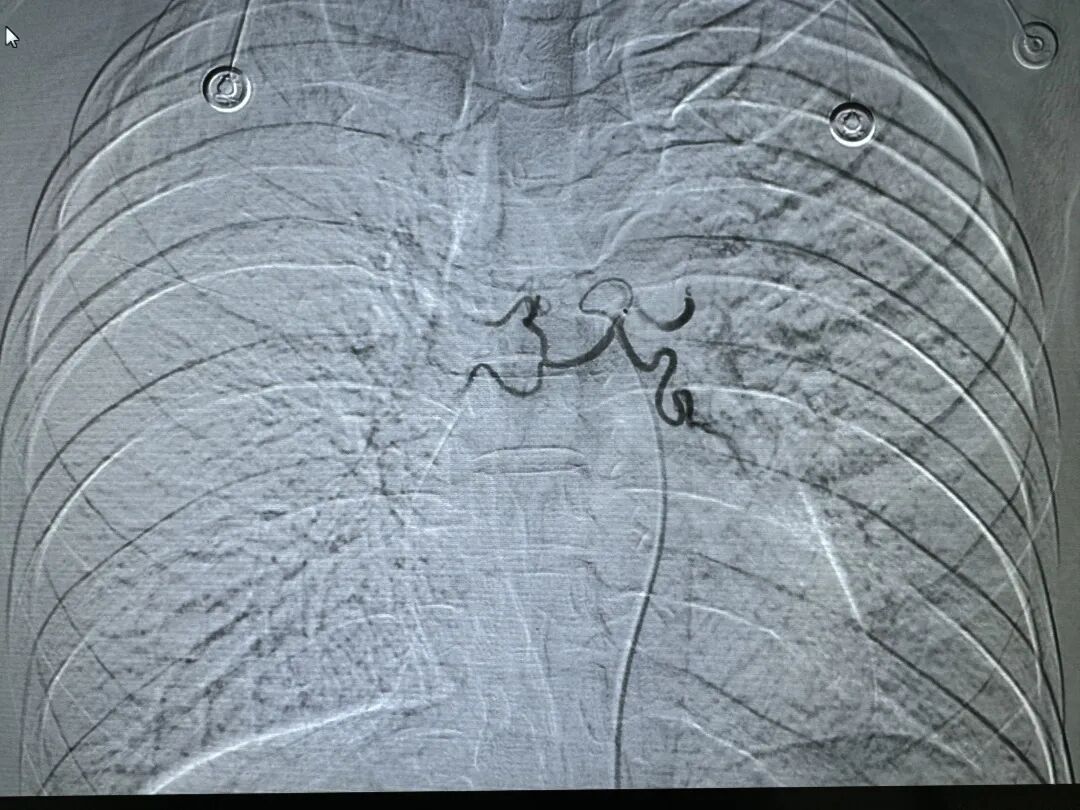

介入手术后,无出血